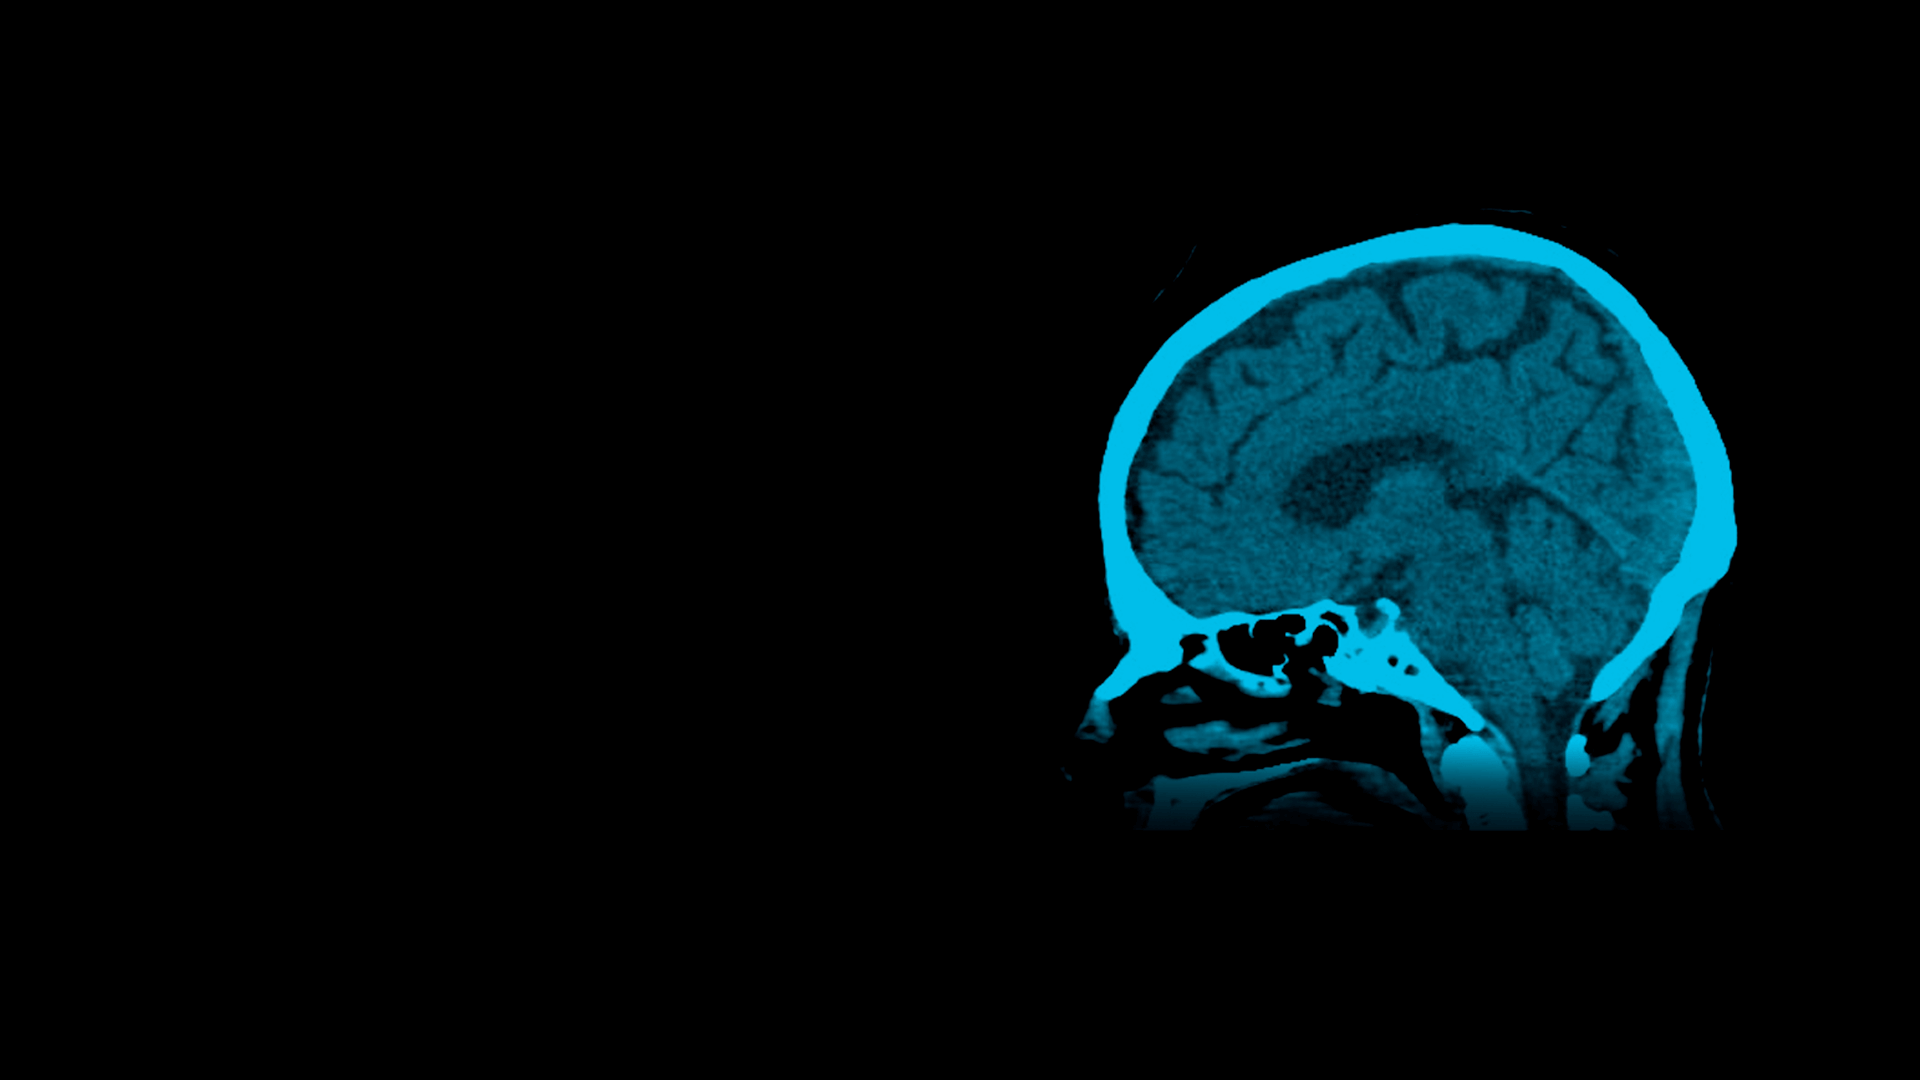

Axial view of a brain MRI scan in shades of blue with the brain structures visible.

TAC | Tomografía Computarizada

Con nuestro servicio de TAC usted obtiene imágenes de alta precisión para detectar enfermedades tumorales, infecciosas, vasculares, degenerativas y evaluar estructuras anatómicas complejas.

Tomografía Computarizada Multicorte que permite obtener imágenes en diferentes planos del cuerpo.